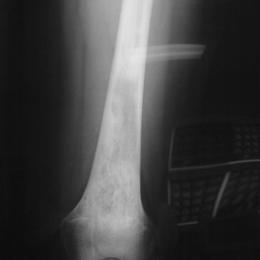

Primary leiomyosarcoma of bone is a rare type of malignant bone tumor. It most commonly occurs in the area behind the tissue that lines the abdomen (the retroperitoneum) and the pelvis. Leiomyosarcoma is also a malignant tumor than can occur in soft-tissue.